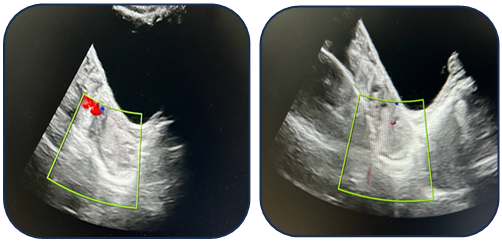

Case 1: A 17-year-old female presented with acute pain. Ultrasound revealed a 95 mm complex left ovarian cyst with no Doppler flow (Fig. 1). Emergency laparoscopy confirmed a 720-degree torsion. Detorsion and cystectomy were performed. Intraoperative findings are shown in Fig. 2, Fig. 3, and Fig. 4. Histopathology reported a serous cystadenoma. Postoperative ultrasound on day 5 confirmed a viable ovary (Fig. 5). | Figure 1. Ultrasound findings of a left ovarian cyst with torsion |